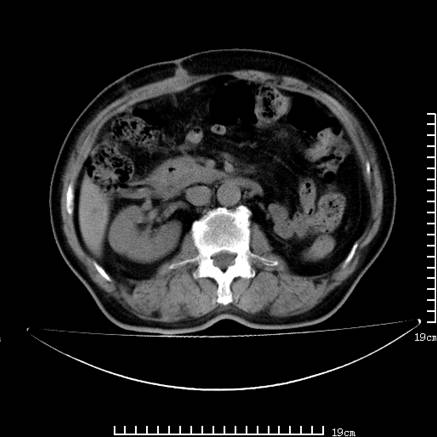

以下是引用zsl6918在2008-7-19 21:53:00的发言:[br]胆总管结石并胆系感染,胆囊切除术后改变。

以下是引用liaoqiang在2008-7-19 22:26:00的发言:[br]胆总管结石伴胆系感染。